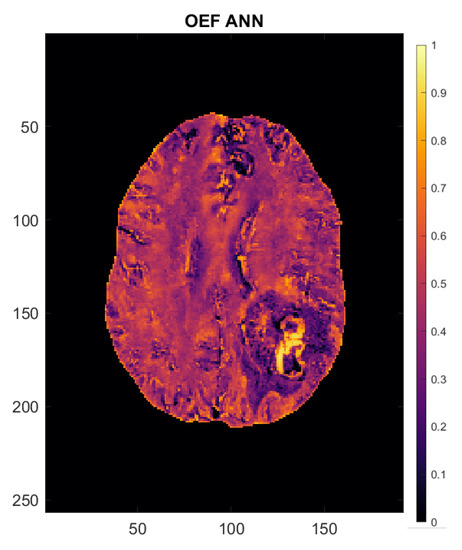

2.3. Image Processing

2.4. Calculation of Perfusion and Oxygenation Parameters

2.5. Artificial Neural Network